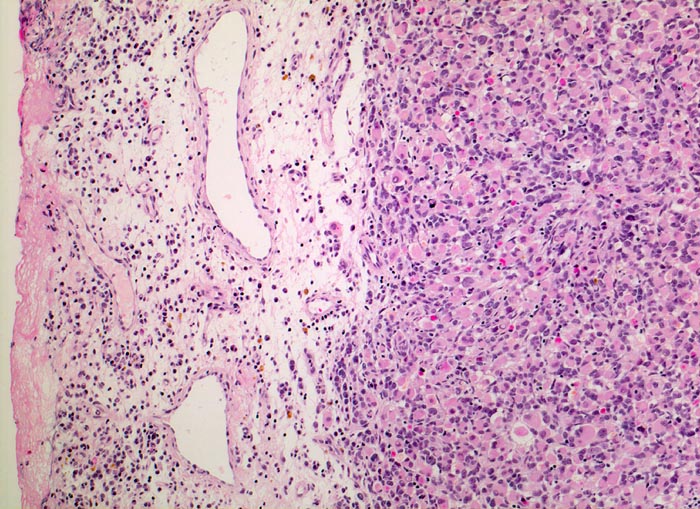

PathoPic – image database / PathoPic ID 5147 - embryonales Rhabdomyosarkom

embryonales Rhabdomyosarkom

Links im Bild ödematöses Bindegewebe mit gemischtem Entzündungsinfiltrat und Blutungsresiduen (braune Hämosiderinablagerungen). Der expansiv wachsende Tumor rechts im Bild hat keine Kapsel und besteht aus kleinen Gruppen primitiver Zellen mit rundlichen Kernen und praktisch fehlendem Zytoplasma sowie zahlreichen zytoplasmareichen Rhabdomyoblasten.

Schmerzloser rasch wachsender Tumor im oberen inneren Quadranten der Orbita mit Verdrängung des Bulbus nach temporal. Diplopie.

Histologie

Vergrösserung